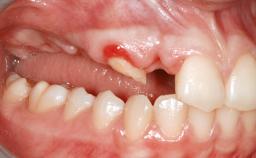

Shell Technique for Horizontal and Vertical Maxillary Bone Augmentation in a Partially Edentulous Patient with Aggressive Periodontal Disease

A 46-year-old woman was referred for treatment whose main complaints were mobility of her fixed partial dentures (right maxilla and left mandible) and periodontal bleeding during function. She also reported having taken systemic antibiotics to treat recurrent swelling in the area of the upper left molars. The patient had not seen a dentist for at least 2 years. She did not smoke and had no history of major systemic disease other than two minor orthopedic procedures some years back. The first-visit examination revealed poor plaque control, tooth mobility, periodontal disease, and a residual dentition widely associated with deep periodontal pockets.

Soft Tissue Anatomy Intact Defective

Bone Volume Horizontally and vertically sufficient Horizontally deficient Deficient vertically or deficient vertically AND horizontally

Bone Volume Deficient vertically or deficient vertically AND horizontally